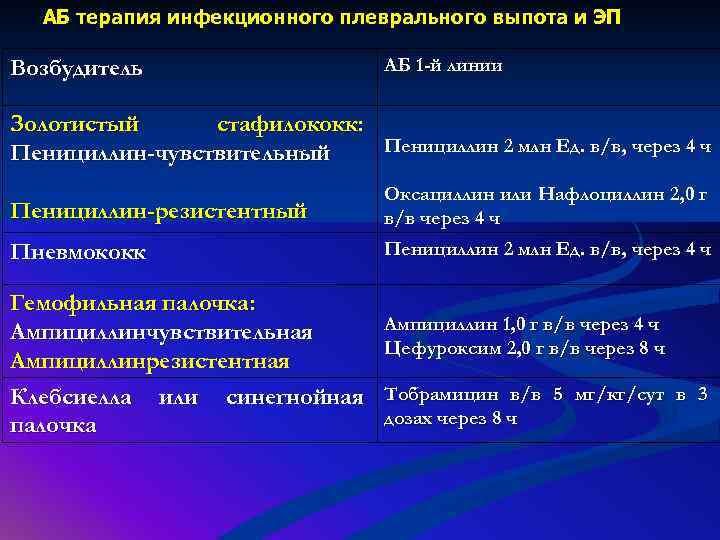

Диагностика плеврального выпота: что нужно знать